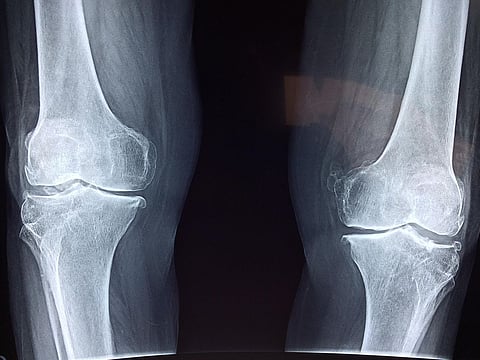

"Joint and muscle pain can also be experienced by doing chores or activities that you haven't frequently done before like sitting cross-legged on the floor, bending from the waist while cleaning or cooking, lifting heavy weights, etc. It has been observed that reduced physical movement has led to increase in pain in the waist and back, legs, knees and hips," underlines the expert.

Reduced physical movement has led to an increase in pain in the waist and back, legs, knees, and hips. Pixabay